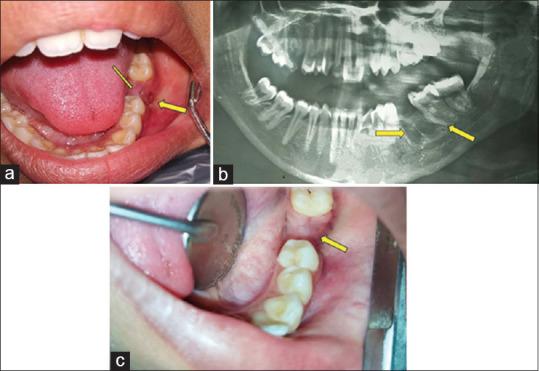

Tuberculosis (TB) is a serious infectious disease with significant mortality and most commonly affects the pulmonary system and rarely the oral cavity. Because oral tuberculosis is a rare disease, it is often overlooked in the differential diagnosis of oral lesions. Despite the recent decline in the incidence of tuberculosis, it remains a highly contagious and serious public health problem, thus requiring early diagnosis and rapid intervention. Extrapulmonary tuberculosis (EPTB) is defined as any bacteriologically confirmed or clinically diagnosed case of tuberculosis (TB). A 17-year-old girl reported at the outpatient Department of Dentistry with the chief complaint of a swelling at the backside of mouth along with pus discharge. She noticed these symptoms approximately one month after the extraction of the left mandibular first molar. The patient was referred to the Department of Pulmonary Medicine for further investigation and treatment. Subsequently, diagnosis of EPOTB was reached on the basis of the histopathological findings and the previous personal as well as family history. Drastic improvement was observed in the general condition and a complete resolution of the oral lesion after four weeks of ATT and the patient was completely free of all the symptoms after six months of follow-up period. This case demonstrated the importance of oral manifestation of oral tuberculosis for dentist who may be the first healthcare provider to encounter a variety of oral lesions.

结核病是一种严重的传染病,死亡率很高,最常累及肺部系统,很少累及口腔。由于口腔结核病是一种罕见疾病,在口腔病变的鉴别诊断中常被忽视。尽管近年来结核病发病率有所下降,但它仍然是一种具有高度传染性的严重公共卫生问题,因此需要早期诊断和迅速干预。肺外结核病(EPTB)被定义为任何经细菌学确诊或临床诊断的结核病病例。一名17岁女孩到牙科门诊就诊,主诉口腔后部肿胀并伴有脓液排出。她在拔除左下颌第一磨牙后约一个月注意到这些症状。该患者被转诊至肺科进行进一步检查和治疗。随后,根据组织病理学检查结果以及既往个人史和家族史确诊为肺外结核病。抗结核治疗四周后,患者的一般状况有了显著改善,口腔病变完全消退,随访六个月后患者所有症状完全消失。该病例证明了口腔结核病的口腔表现对于牙医的重要性,因为牙医可能是首个遇到各种口腔病变的医疗服务提供者。